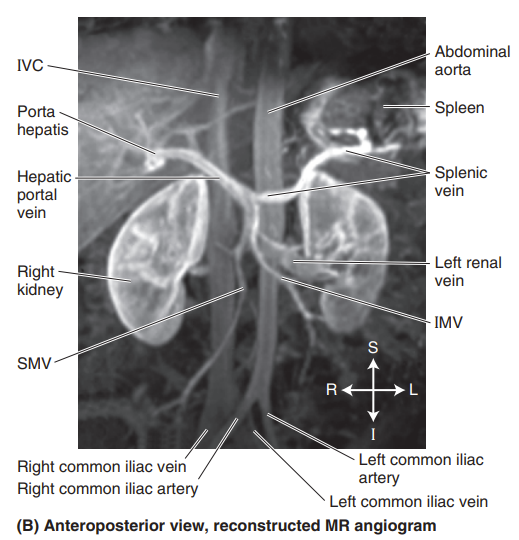

Please label the reconstructed MR angiogram